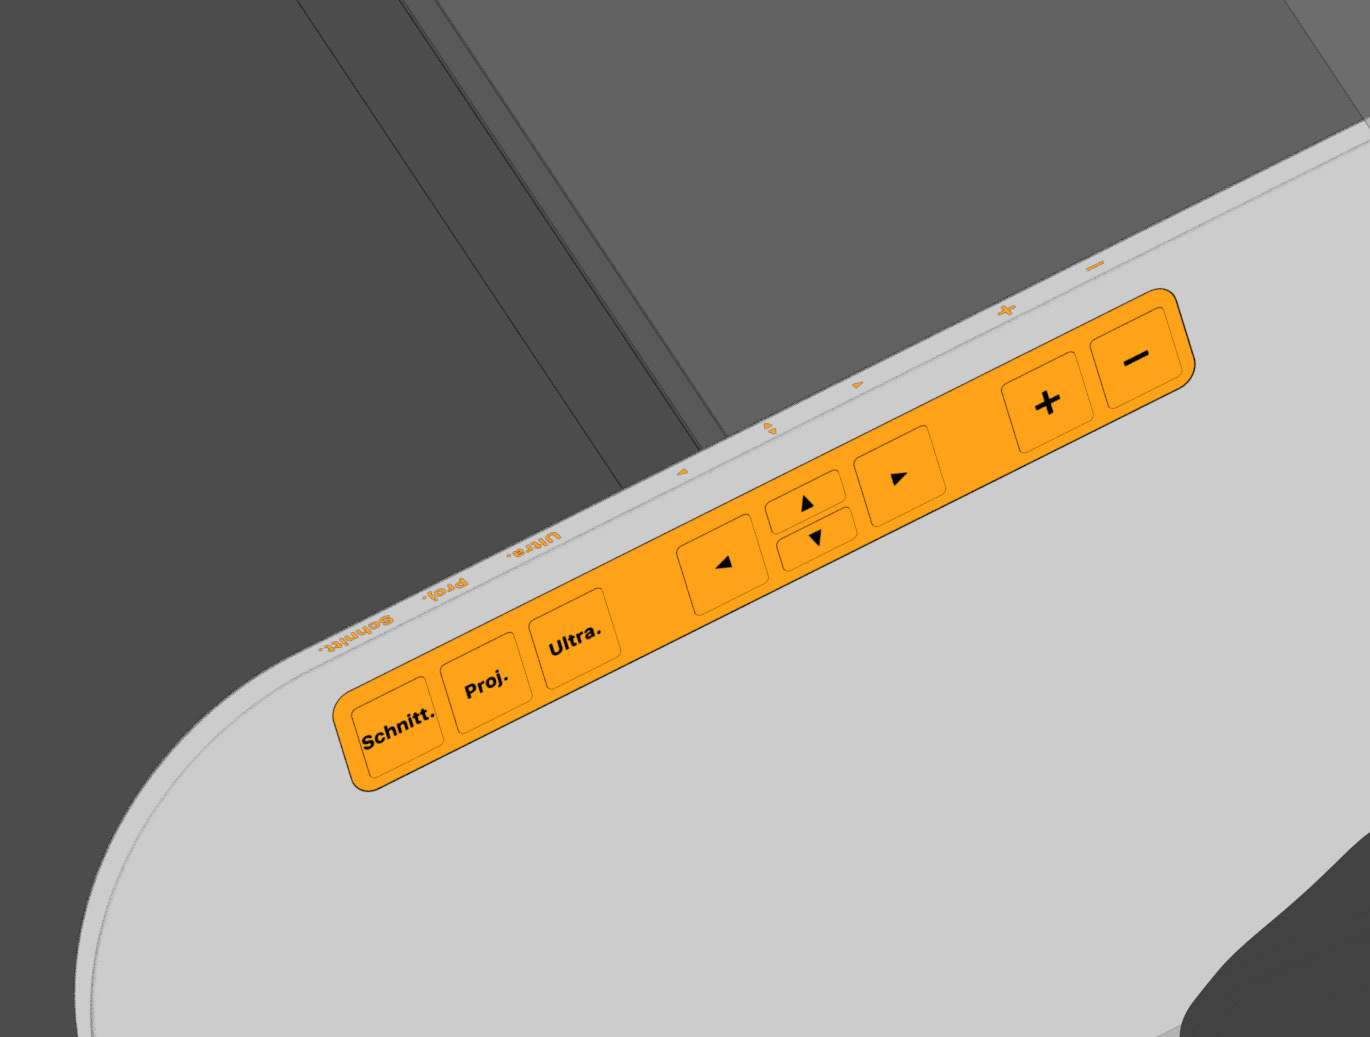

For direct inspection of the CT scans, there is one large overview screen per side and a small detail screen inside the gantry. The control interface of the gantry is located inside the lower trough, which protects the abdomen of the interventionists from radiation. In addition, there is a foot pedal on the floor that allows hands-free activation of the CT imaging.

Silicone Button Interface

Silicone Button Interface